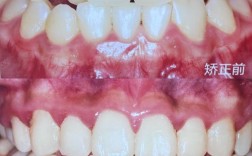

笑容是颜值的“加分项”,而牙齿整齐度直接影响笑容质量,矫正前,牙齿拥挤、错位可能导致微笑时牙齿露出的数量不对称(如一侧露8颗,一侧露6颗)、牙龈暴露过多(“露龈笑”与牙齿位置相关),或牙齿形态不协调(如“虎牙”外突显得突兀),矫正后,牙齿排列整齐,上下牙弓对称,微笑弧度自然,笑容线(上唇缘与牙齿上缘形成的曲线)会更流畅,整体笑容更显干净、亲切,这种“笑容美学”的提升往往让人看起来更年轻、有活力。